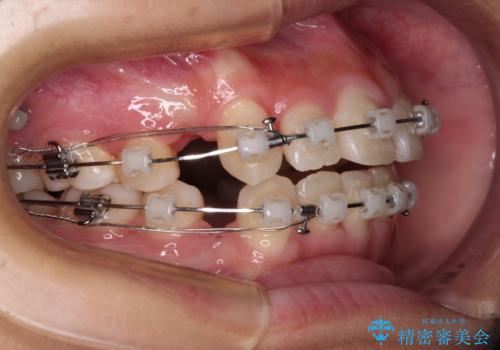

上顎骨幅が狭い 急速拡大装置を併用した抜歯矯正

検査を行った結果、上顎骨の横幅が相対的に狭いことが分かり、叢生が強いことから、急速拡大装置にて上顎骨を側方に拡大することで、叢生の解消と奥歯の咬み合わせ改善を図ることとしました。

一般的には上下左右の第一小臼歯4本を抜歯する必要がありますが、拡大量によっては非抜歯矯正の適用となる可能性があるため、まずは非抜歯矯正で治療を開始し、抜歯が必要と判断された時点で速やかに4本抜歯を行うこととしました。

急速拡大後、歯列はきれいに並んだのですが、口元が出っ歯になってしまったため、速やかに抜歯を行い、治療期間がいたずらに遅延することのないようにしました。